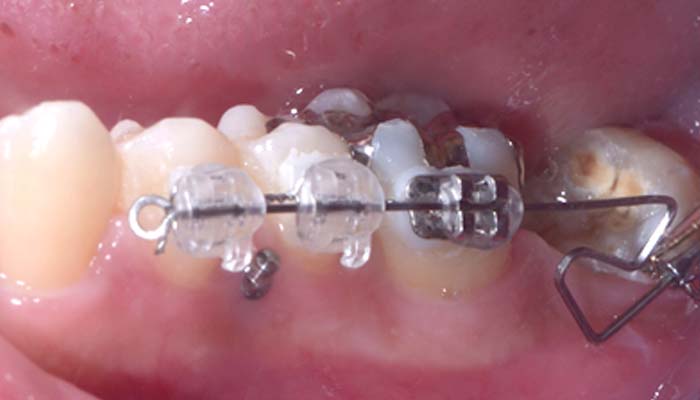

治療例12. 上下の部分矯正

治療前

経過

治療後

主訴 | 八重歯と咬み合わせを治したい |

---|---|

治療期間 | 9ヶ月 |

治療費 | 40万+tax (別途調整料) |

治療内容 | 上下顎ラビアル矯正(表側矯正) |

治療のリスク | 後戻り |